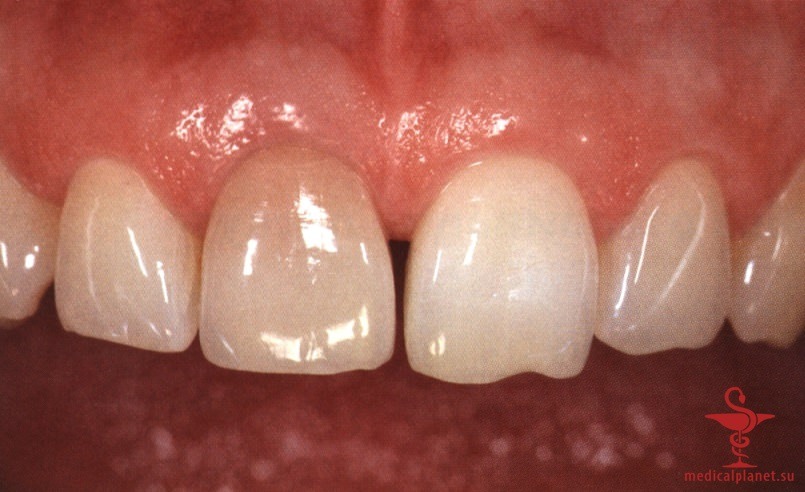

Более того, происходит потеря объема трансплантата, а результат редко можно признать оптимальным, особенно в области десневых сосочков (рис. 2), поэтому в настоящее время такой протокол не рекомендуется.